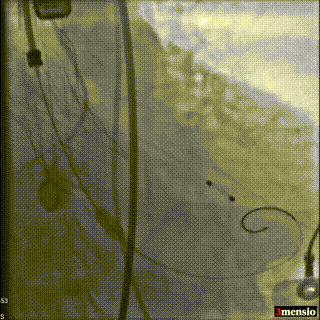

根部造影,可见明显反流,猪尾在右窦

调整猪尾到无窦,输送器跨瓣,确认位置

起搏状态下释放,造影观察瓣膜位置

第一次释放下滑,重新回收定位